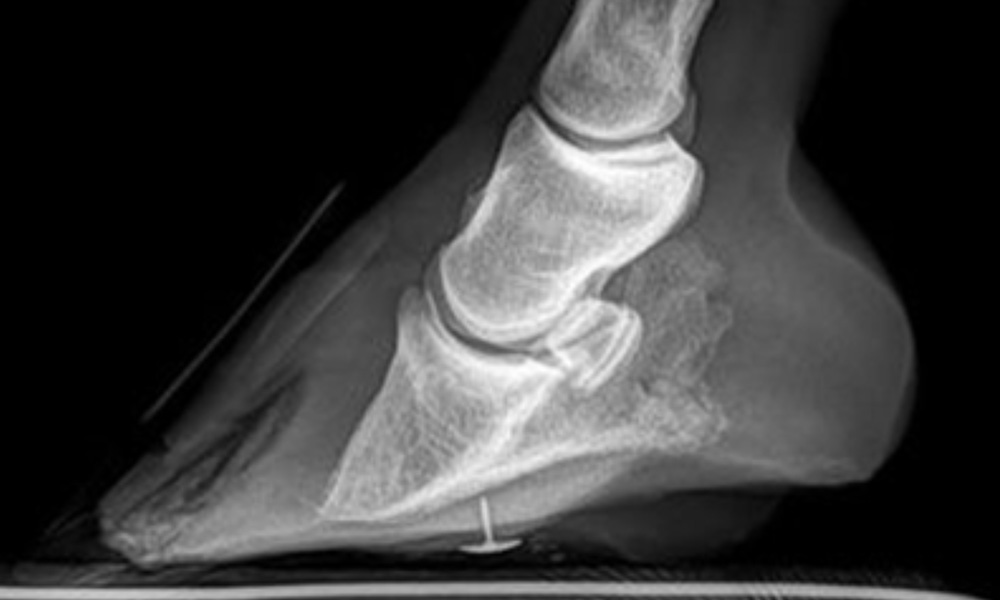

Laminitis

Laminitis is an extremely painful condition affecting a horse/pony’s feet during which inflammation of the laminae (the connective tissue holding the pedal bone to the hoof wall) causes instability of the structures within the hoof.

Laminitis can be considered a risk at any time of year, but is commonly seen in Spring time.